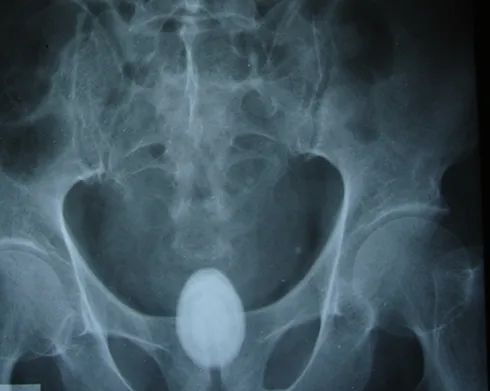

Sau khi chụp phim X- quang, siêu âm các bác sĩ phát hiện ra viên sỏi lớn nằm trong bàng quang bệnh nhân.

Ekip bác sĩ Bệnh viện Hoàn Mỹ, Đà Lạt, đã tiến hành ca phẫu thuật trong vòng 1 giờ lấy ra viên sỏi từ bàng quang bệnh nhân có kích thước 10cm x 7cm, nặng 900gram.

Bác sĩ Vinh cho biết bệnh nhân có sỏi bàng quang lớn như trường hợp ông K’ Tiêng là rất hiếm.

Viên sỏi nặng 850 gam lấy ra từ bàng quang ông K’ Tiêng - Ảnh: C.Thành

Thông thường sỏi bàng quang chỉ to bằng đầu ngón tay và bác sĩ có thể chữa khỏi theo phương pháp tán sỏi ngoài cơ thể.